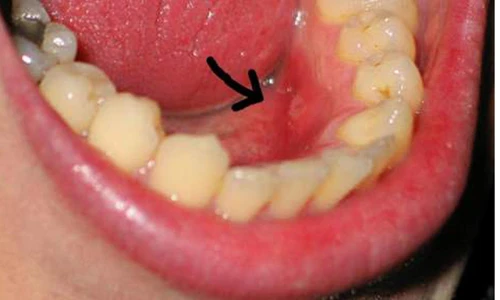

Kiểm tra răng và nướu. Người mắc ung thư miệng còn gặp triệu chứng răng, nướu răng sưng vù, đỏ, nổi cục trong thời gian dài. Đối với người sử dụng răng giả, các vấn đề về nướu sẽ khiến chiếc răng nhân tạo không còn đáp ứng được nhu cầu ăn nhai.